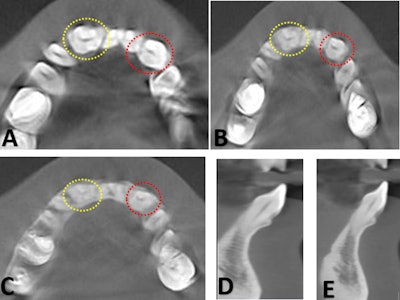

(A) Intraoral photograph showing bilaterally fused mandibular lateral incisors and canines with visible developmental grooves on the labial surfaces and mild tooth surface loss in relation to teeth #42 and #43. (B,C) Intraoral periapical radiographs demonstrating bilateral fusion of the mandibular lateral incisors and canines, with two distinct coronal pulp horns converging into a single pulp chamber at the cervical level. (D) Mandibular occlusal radiograph confirming bilateral fusion of the lateral incisors and canines.Images and captions courtesy of Selvaraj et al. Licensed under CC BY 4.0 International.

Periapical x-rays revealed that her fused teeth showed a single root with a single canal, and this was confirmed on cone-beam computed tomography (CBCT). Furthermore, the fused teeth looked very similar on imaging.